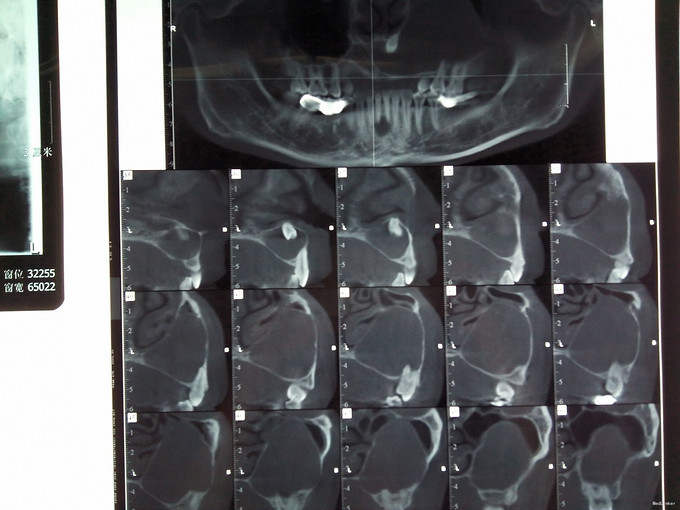

检查:口外检查:左侧鼻唇沟区轻微隆起,鼻唇沟较右侧稍浅,表面皮肤无红肿破溃,无明显压痛,无乒乓球样感。 口内检查:左上颌唇侧前庭沟轻微隆起,触诊无乒乓球样感及波动感,无压痛,腭侧未见明显骨质膨隆,41舌侧牙色充填物,31,41叩(±),松(I),冷热测无反应,牙髓活力测试无活力,牙龈正常,余牙及粘膜未见明显异常。 辅助检查:外院全景片示11至28根尖区可见一明显类椭圆形透射影,边界较清,约6.0*4.0cm大小,其内含一多生牙牙冠,41根管内致密充填影像,31,41 根尖周可见小范围低密度影. 全景片及CBCT片如图

诊断:1.左上颌骨囊肿:含牙囊肿? 2.上前牙去多生牙 3. 31,41慢性根尖周炎 治疗方案:1.全麻下行左上颌骨囊肿刮除术+上前牙区埋伏多生牙拔除术, 2.术后择期治疗下前牙 治疗: 常规全麻消毒铺巾,切开翻瓣,颌骨开窗,显露囊肿,见囊肿壁薄,囊壁已破溃,灰褐色豆渣样物质,剥离囊肿,拔除多生牙,冲洗,妥善止血,缝合。术后病理结果示左上颌骨含牙囊肿。转诊牙体择期治疗下前牙。